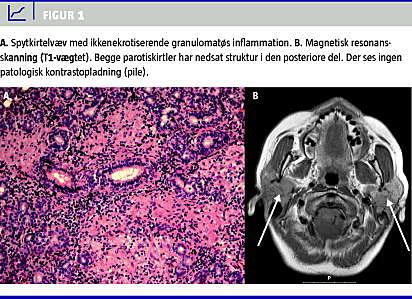

MR-skanningen viste bilateral affektion i begge parotisregioner (Figur 1 ). Ved PET/CT'en fandt man øget optagelse i glandulae parotis, mediastinum omkring hilusregioner og i venstre overarmsknogle. CT'en viste forstørrede lymfeknuder i mediastinum og i begge hilusregioner. Lungeparenkymet var uden infiltrater.

For at få en endelig diagnose og for at udelukke lymfom blev der foretaget en kilebiopsi fra højre glandula parotis. Histologien kunne bekræfte den cytologiske diagnose: ikkenekrotiserende granulomatøs inflammation, og patienten blev henvist til medicinsk afdeling med henblik på videre udredning og behandling.